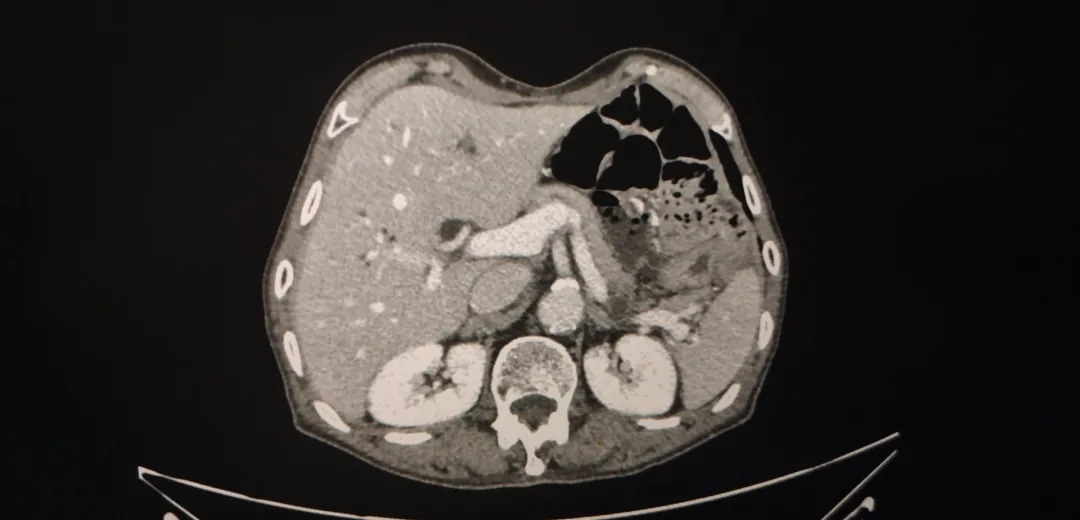

腹盆腔强化CT(2018-4-4):1、胃体及胃窦胃壁增厚,考虑胃癌;2、胃周、胃左动脉区及腹膜后多发肿大淋巴结,考虑转移;3、肝内胆管结石,肝内胆管轻度扩张;4、左肾囊肿,左肾上腺增厚,考虑增生;5、前列腺增生伴钙化;6、盆腔少量积液;7、两下肺实变索条,左侧胸腔少量积液。

图1-1 2018-4-4 箭头为胃周肿大淋巴结

图1-2 2018-4-4 箭头为胃部肿瘤,胃壁增厚明显